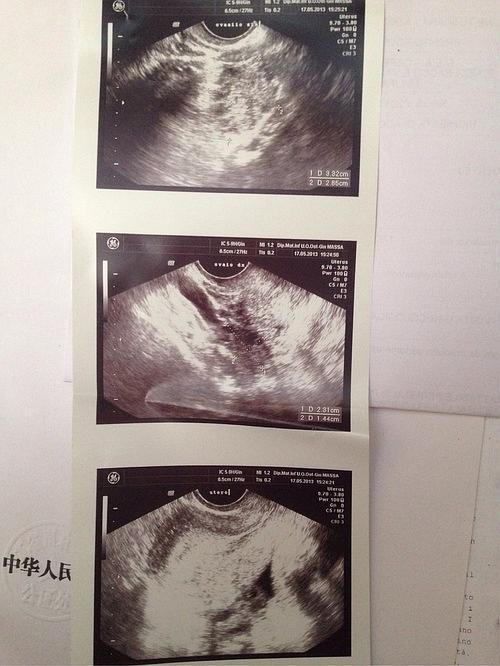

今天做阴超,说我子宫内膜不均匀,有薄有厚.

阴超子宫

阴超图子宫

阴超图解

阴超检查图片